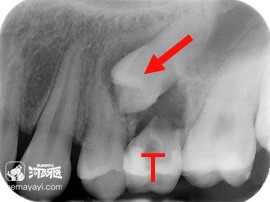

“六龄齿”会阻生。如果“六龄齿”的萌出方向异常,尤其是近中向萌出时在第二乳磨牙远中颈部形成阻力,就会产生阻生。

“六龄齿”也叫第一恒磨牙,它的位置对整个牙弓其他牙齿的正常萌出有重要的影响,需要及时予以纠正。家长必须重视这个问题,因为在孩子恒牙咬合建立初期,及时把问题解决了,往往能起到事半功倍的效果。

正畸医生会根据阻生的严重程度采用不同的处理办法。轻、中度的阻生可以借助分牙铜丝、分牙圈或分牙簧,在第二乳磨牙和第一恒磨牙间形成分力,直立阻生牙,使阻生牙可以顺利萌出;重度阻生可以制作矫治器进行牵引,使阻生牙直立萌出;有一些比较复杂的还需要开窗牵引导萌。